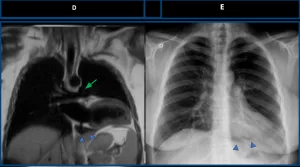

Coronal T2-weighted MRI (D) demonstrates interposition of lung tissue in the aortopulmonary window (green arrow), as well as lung interposed between the diaphragm and the cardiac base (blue arrowheads). Frontal chest radiograph (E) also shows lung interposition between the diaphragm and the inferior cardiac border (blue arrowheads), consistent with left pericardial agenesis.